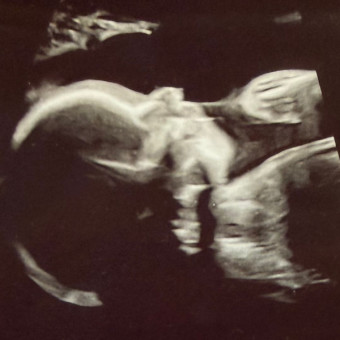

Baby Shiple

Megan & Ben Shiple

Bowling Green, OH

July 3, 2026

To our family and friends we are so grateful for you and all the love and support you have shown us. We can’t wait to celebrate with you to bring our sweet baby girl into the world. 🩷